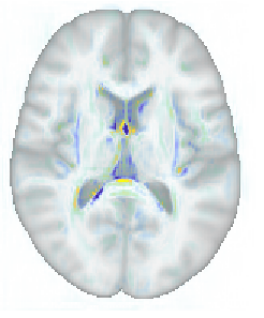

A key advantage of the proposed method over discriminative methods such as RVoxM and SFCN is that, in addition to the discriminative map that it uses to make predictions, it also computes a generative map that expresses the causal effect of the variable of interest on brain morphology. To illustrate why this is important, Fig. 9 shows, for three different training set sizes, the discriminative map computed by our method for predicting age, along with the corresponding discriminative map of RVoXM and the SmoothGrad saliency map (Smilkov et al., 2017) – a generalization of linear spatial maps to nonlinear methods (Adebayo et al., 2018) – of SFCN. The inconsistencies of these maps across both the training set sizes and the different methods, and their overall lack of correspondence with the known neurobiology of aging, illustrate the difficulty of using discriminative maps for human interpretation.

More insight can be gained by examining the proposed method specifically, since it uses disciminative maps that are derived from generative ones. It is worth noting that estimating the generative maps from training data is itself quite stable, since it merely amounts to fitting two basis functions to hundreds of measurements in each voxel (cf. (8)). Furthermore, as illustrated in Fig. 10, the resulting maps are intuitive to interpret, since they show typical age-related effects such as cortical thinning and ventricle enlargement (Fjell et al., 2009; Fjell and Walhovd, 2010). When the discriminative maps are subsequently computed as , however, a strong dependency on the training set size is introduced, because the method explicitly controls the complexity of its noise model in response to the size of the available training set (the bias-variance trade-off of Sec. 4.4). can also capture peculiarities in the data that may be relevant for improving prediction performance, but not for human interpretation. An example of this was shown in Fig. 5, where overall brightness variations and residual MR bias field artifacts were picked up by the noise model. Through , such noise patterns can find their way into , producing hard-to-interpret spatial maps that no longer reflect the expected age-related brain atrophy patterns. This is clearly illustrated in Fig. 4, where the discriminative map is contrasted with the corresponding generative map .